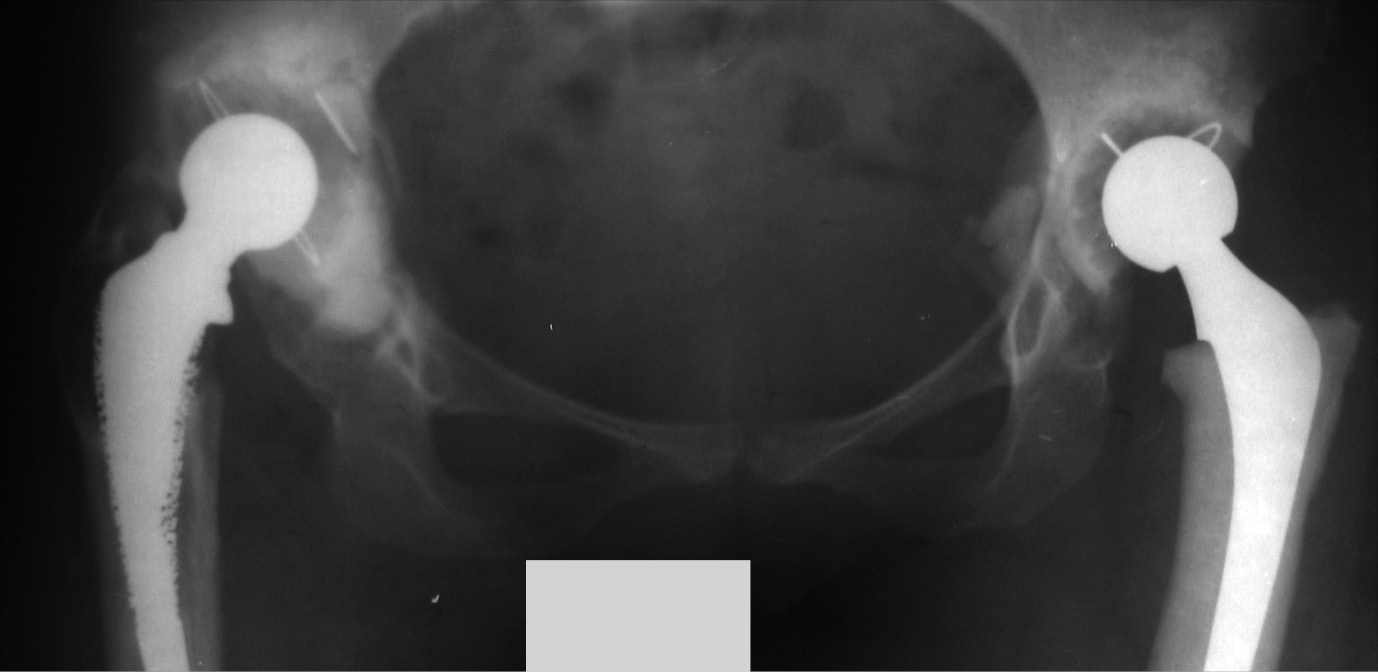

В октябре 2019 г. пациентка обратилась на консультативный прием с жалобами на боли и ощущение нестабильности в правом тазобедренном суставе при незначительной физической нагрузке (рис. 9).

Рис. 9. Рентгенограмма таза при поступлении в клинику для ревизионного эндопротезирования правого тазобедренного сустава в 2019 г.

После выполнения обзорной рентгенографии таза с захватом тазобедренных суставов выявлена нестабильность тотального эндопротеза правого тазобедренного сустава: обширные сегментарные дефекты вокруг вертлужного компонента, миграцию вертлужного компонента медиально и краниально, резорбция костной ткани вокруг бедренного компонента в 1, 2, 6 и 7-й зонах Груена. Рентгенологически дефект вертлужной впадины был оценен как тип IIIB по классификации W.G. Paprosky (рис. 1).